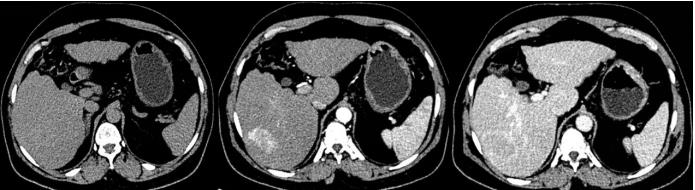

3.下图中肝硬化的CT表现描述错误的是:

A、肝内大小不等结节

B、肝脏表现凹凸不平

C、脾大

D、肝硬化增生结节增强后明显强化

A: 肝硬化再生结节大多增强动脉期无强化,强化形式和肝脏同步

答案: 【 肝硬化再生结节大多增强动脉期无强化,强化形式和肝脏同步】